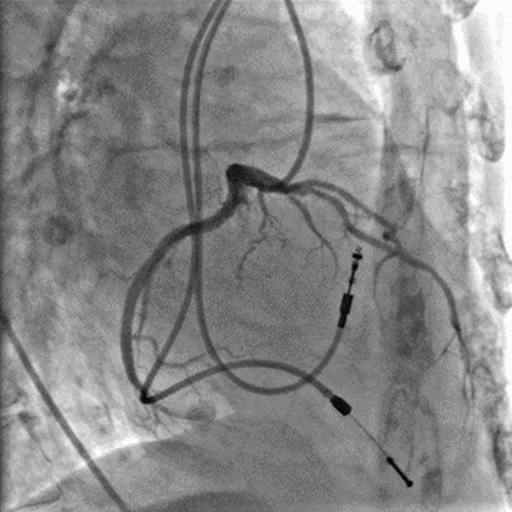

INFX-9000F 血管造影系统可以保证医生在精准手术过程中看到高清晰度的图像。简洁的C 臂不仅具有宽泛的投照范围,而且方便安装,减少不必要的天花板装修工作。

精细图像,纤毫毕现

高精度的诊断和治疗